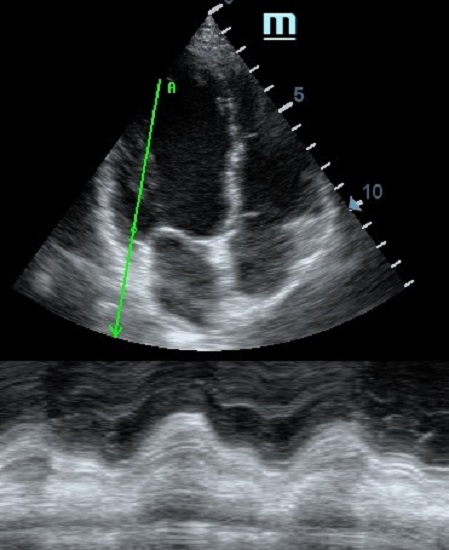

TAPSE - показатель амплитуды движения латеральной части кольца трикуспидального клапана, позволяет количественно и быстро оценить систолическую функцию правого желудочка, норма которого составляет более 17 мм. Главным условием является проведение линии М-режима параллельно стенке правого желудочка в апикальном четырех камерном сечении, что легко достигается при Free Xros.